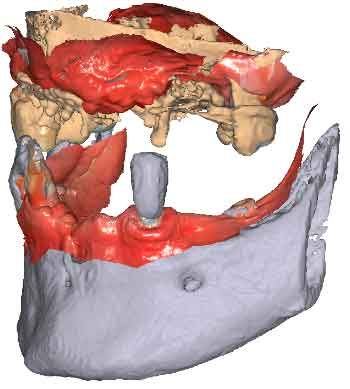

3D models - Bite scan from intra-oral scanner

To be able to use CBCT data as initial models, we need to transform the DICOM file into an STL file.

Discover more about the CBCT segmentation and the integration in TWIM software

By importing patient DICOM files instead of the IOS scans, clinicians can register jaw motion, facilitating precise treatment planning.

Import the segmented and converted CBCT models as initial models in TWIM